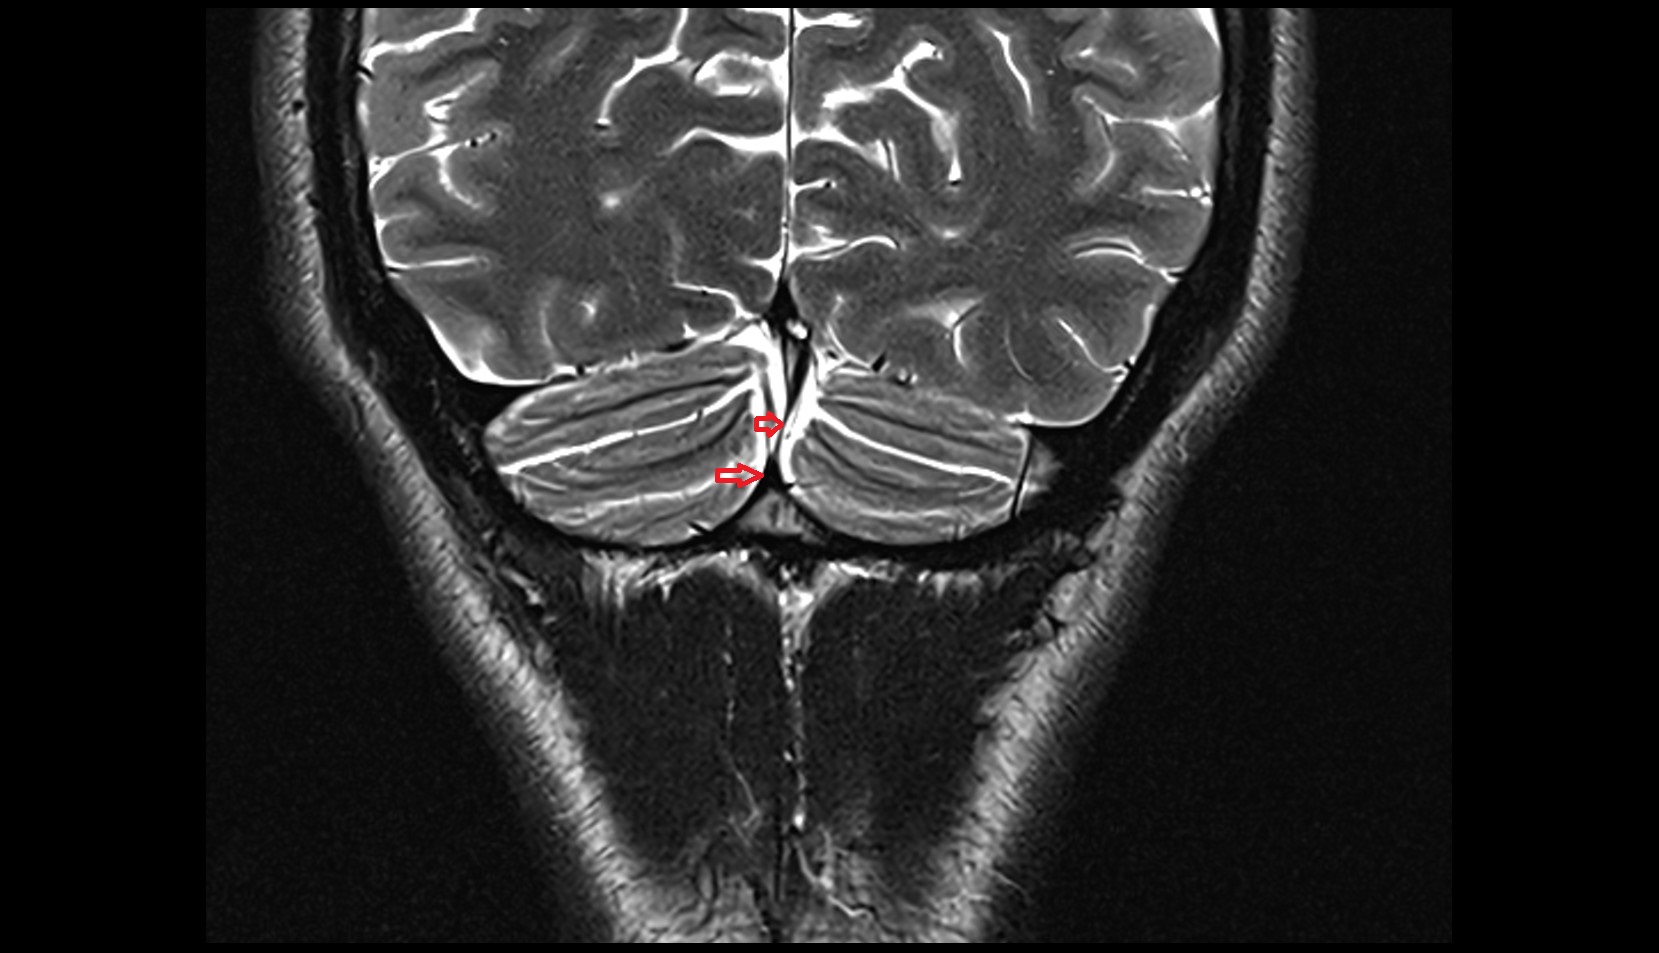

- Cerebellar tonsil (H IX)

- Tonsil of cerebellum